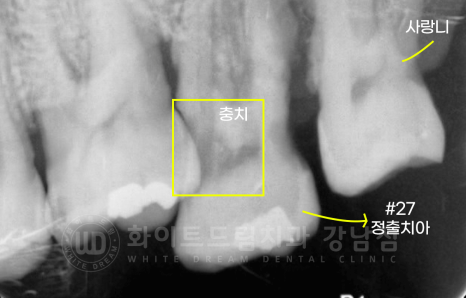

20번대 : 37번 치아 상실로 27번 치아 정출

잠깐! 치아 정출이란?

치아 정출은 대합치가 없을 때 치아가 아래나 위로 이동하는 성질을 이야기합니다.

환자분의 27번 치아처럼 정출이 심하면 교합 & 임플란트 크라운 수복 불가능의 문제로 발치를 할 수밖에 없지만

정출이 심하지 않으면 신경치료 후 크라운으로 진행하기도 합니다.